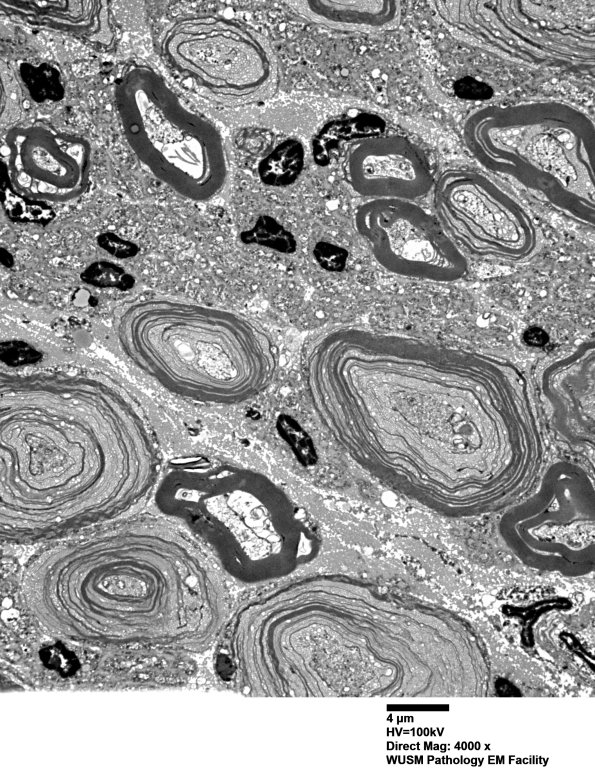

Most myelinated axons, large>small, are involved by vesicular myelin change. All axons show decomposition including unmyelinated axons. (electron micrographs)